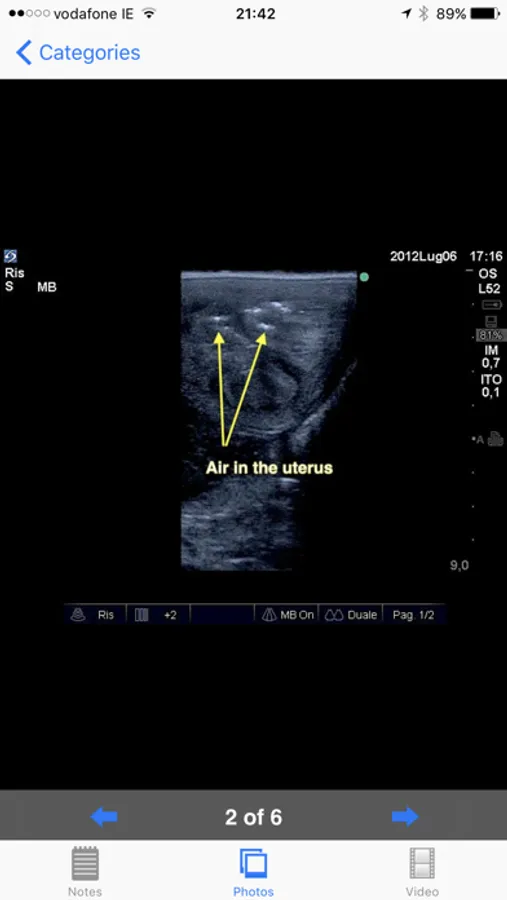

Equine reproductive ultrasound is a comprehensive guide to the examination of the equine female reproductive tract. It features high quality labeled pictures clearly demonstrating the important structures. Furthermore, every phase and condition discussed features high quality ultrasound video loops. All of the pictures and videos are on the phone or iPad and no internet connection is required after the first use.

Developed by Dr Marco Livini, past coordinator of SIRE (Italian Society of Equine Reproduction) and past President of SIVE (Italian Society of Equine Practitioners), the App provides extensive notes, still ultrasonographic images and videos.

•Abnormal uterine involution